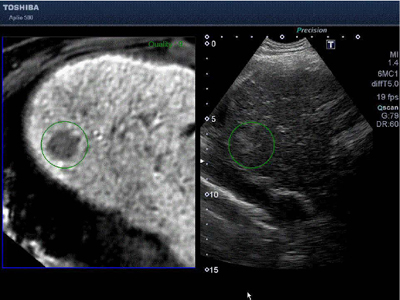

肝細胞がんのスクリーニングに有用とされている,EOB・プリモビスト造影剤を用いたMRI検査により病変が検出された場合も,そのMRI画像データを利用して,超音波ガイド下で穿刺することが可能となる。(図1)

図1 EOB・プリモビスト造影剤を用いたMRI検査により検出された病変のFusion画像

Smart Fusion機能は既得のCTやMRI画像の情報を利用し,超音波診断画像のリアルタイムな動きに連動させ,病変検出をサポートする機能。磁場発生ユニットと,超音波プローブに取り付けた磁気センサより,磁場空間における超音波プローブの位置,角度をリアルタイムで検出する。この検出した位置,角度情報を用いて,超音波プローブが描出しているものと同じ断面を超音波診断装置の画像表示器に表示する。